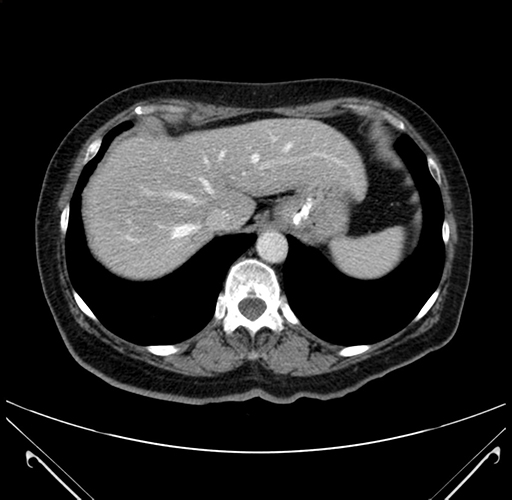

Pre-Chemo: Axial Venous

Axial Venous